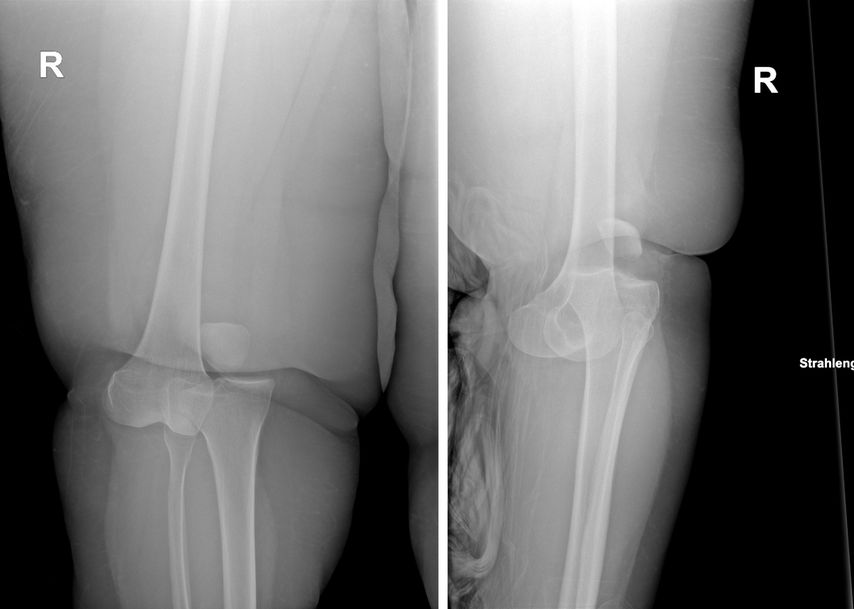

Abb. 1: Röntgenbild einer anterolateralen Knieluxation bei einem „Ultra low energy“-Trauma; links die a.p. Aufnahme, rechts die sagittale Aufnahme